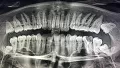

У меня заболели нижние зубы, потом начало отдавать в верхние. Сходила к дежурному врачу на приём. Он определил, что боль идет от восьмерки снизу, положил лекарство, сказал, если будет болеть, необходимо идти удалять. Сходила удалила, т.к. болело пол челюсти.

Конечно, сразу не пройдёт, но диагноз доктора нужно перепроверить.